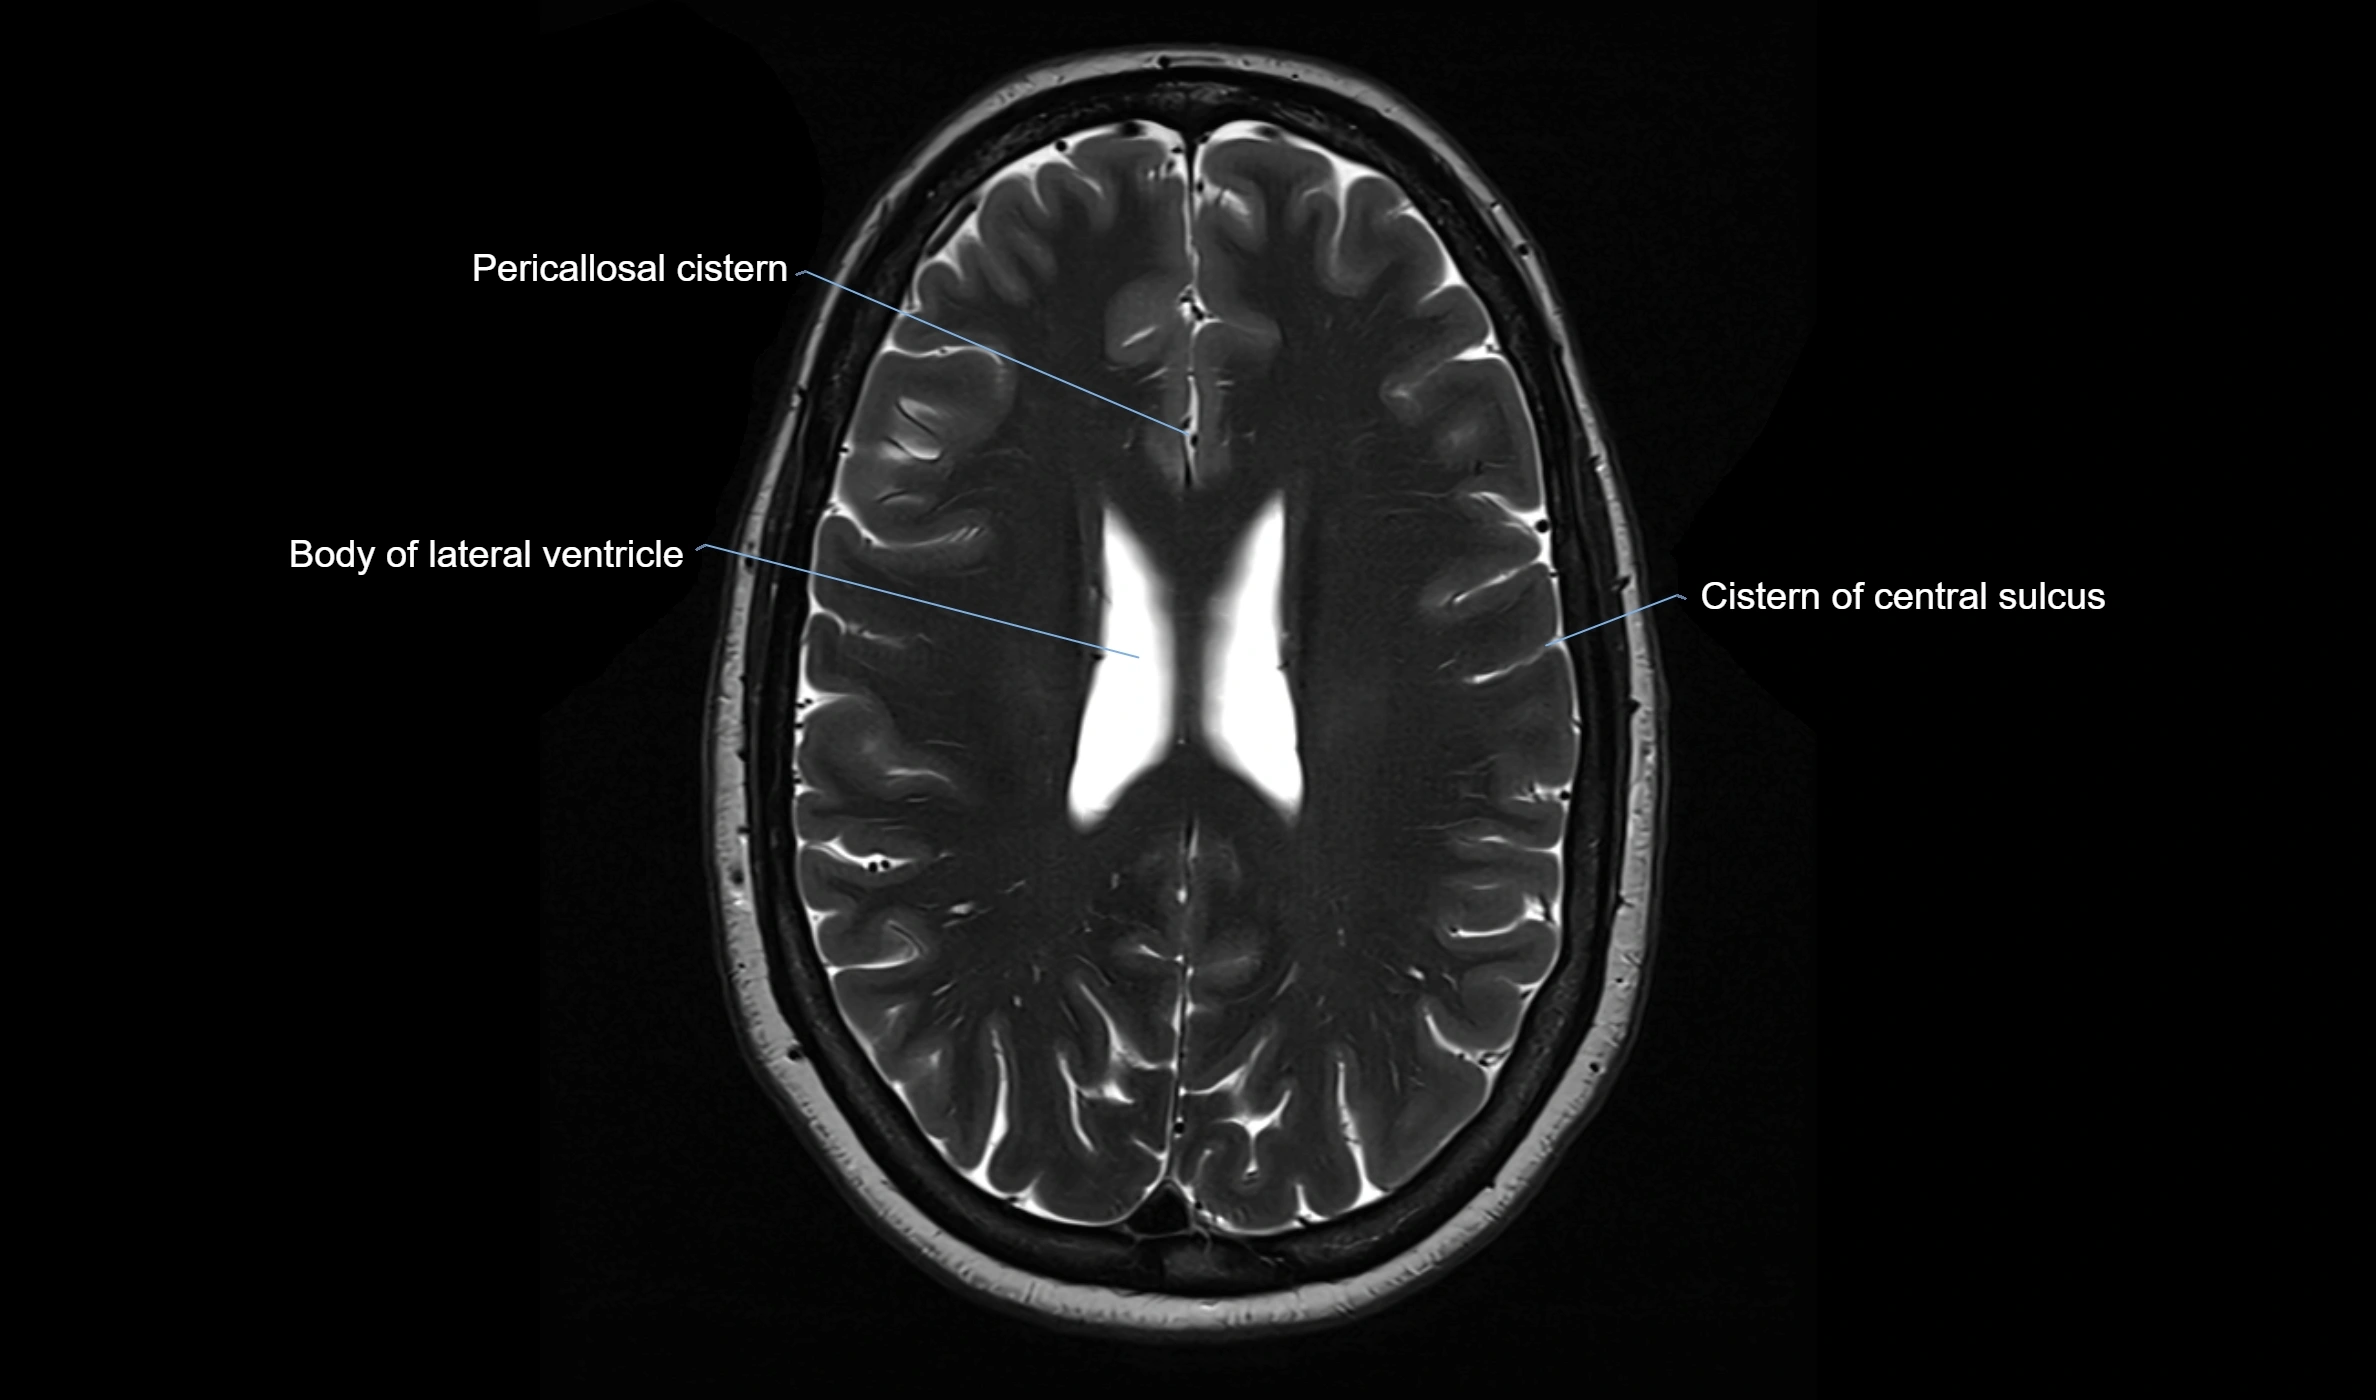

MRI images

image